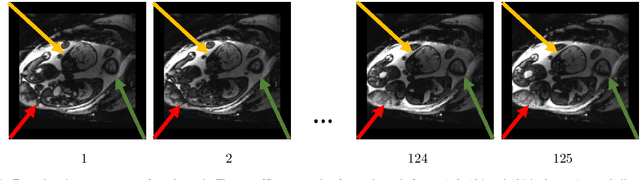

Abstract:We present a robust method to correct for motion in volumetric in-utero MRI time series. Time-course analysis for in-utero volumetric MRI time series often suffers from substantial and unpredictable fetal motion. Registration provides voxel correspondences between images and is commonly employed for motion correction. Current registration methods often fail when aligning images that are substantially different from a template (reference image). To achieve accurate and robust alignment, we make a Markov assumption on the nature of motion and take advantage of the temporal smoothness in the image data. Forward message passing in the corresponding hidden Markov model (HMM) yields an estimation algorithm that only has to account for relatively small motion between consecutive frames. We evaluate the utility of the temporal model in the context of in-utero MRI time series alignment by examining the accuracy of propagated segmentation label maps. Our results suggest that the proposed model captures accurately the temporal dynamics of transformations in in-utero MRI time series.

Abstract:We present a robust method to correct for motion and deformations for in-utero volumetric MRI time series. Spatio-temporal analysis of dynamic MRI requires robust alignment across time in the presence of substantial and unpredictable motion. We make a Markov assumption on the nature of deformations to take advantage of the temporal structure in the image data. Forward message passing in the corresponding hidden Markov model (HMM) yields an estimation algorithm that only has to account for relatively small motion between consecutive frames. We demonstrate the utility of the temporal model by showing that its use improves the accuracy of the segmentation propagation through temporal registration. Our results suggest that the proposed model captures accurately the temporal dynamics of deformations in in-utero MRI time series.